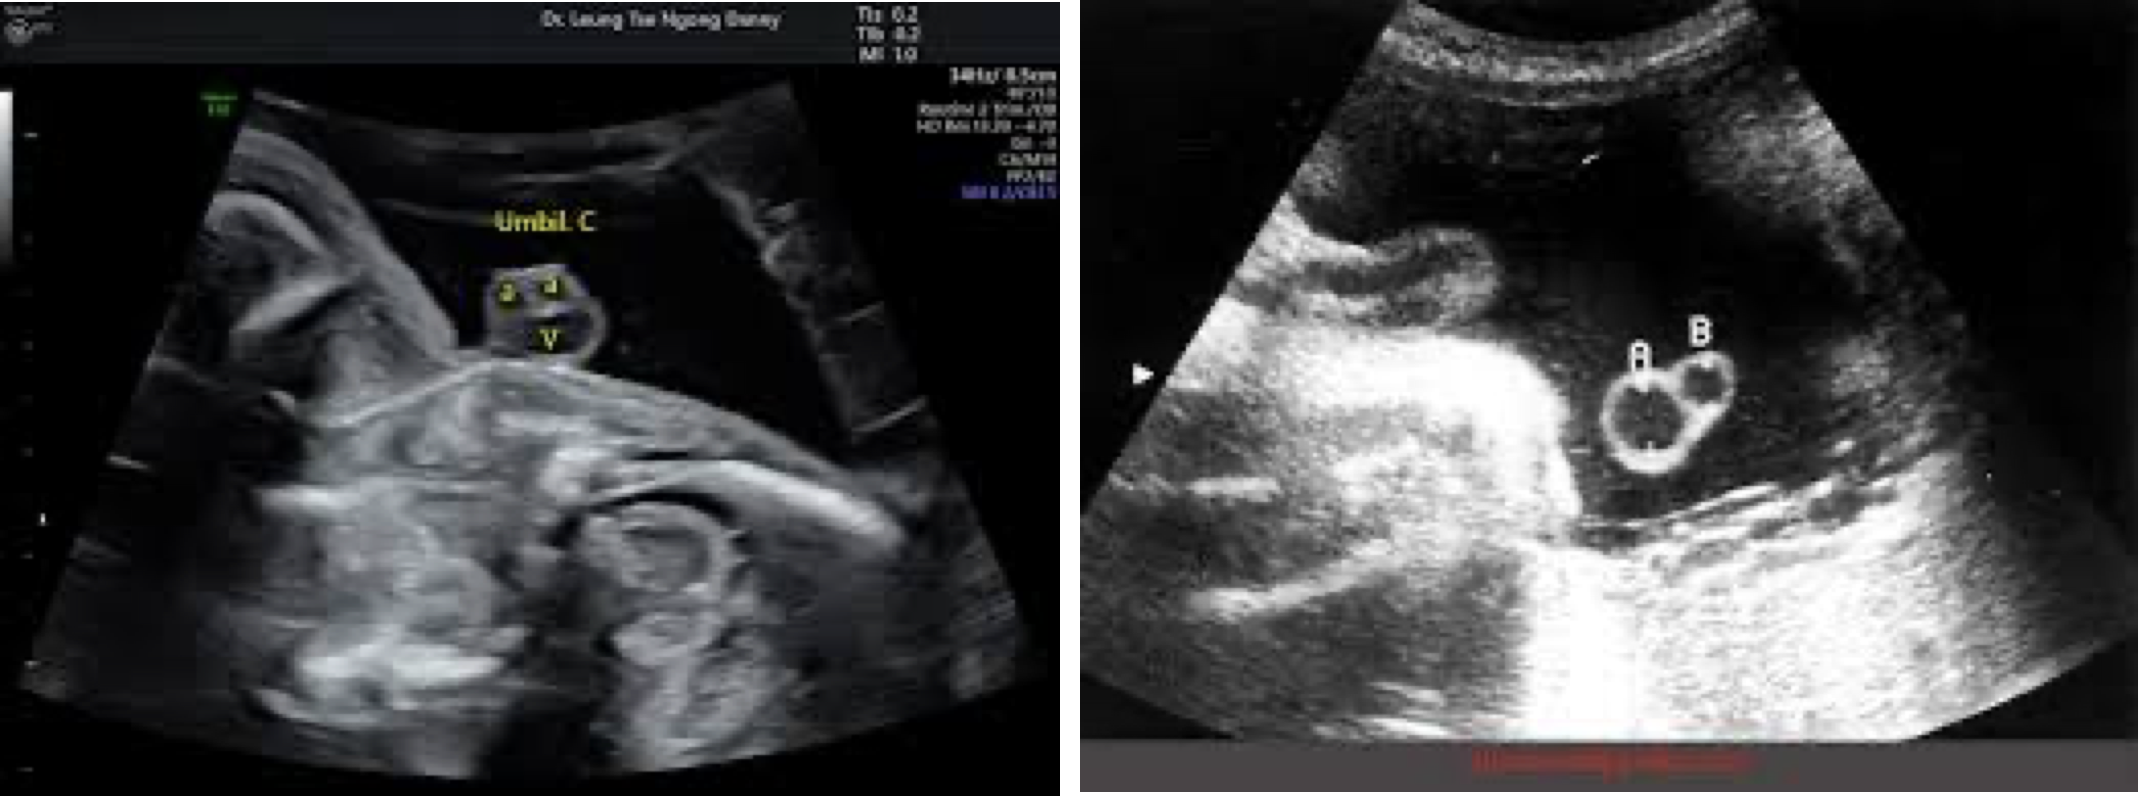

단일 제대 동맥 (Single Umbilical Artery)

정의: 정상 탯줄(좌, 2동맥 1정맥)과 달리 1개의 제대 동맥 만 존재하는 경우(우).

특징: 신생아의 약 0.5-1%에서 발견되는 비교적 흔한 이상. 단독으로 나타나는 경우가 많으나, 약 20-30%에서 다른 구조적 기형(특히 신장, 심장)을 동반할 수 있어 관련 정밀 초음파 검사가 필요